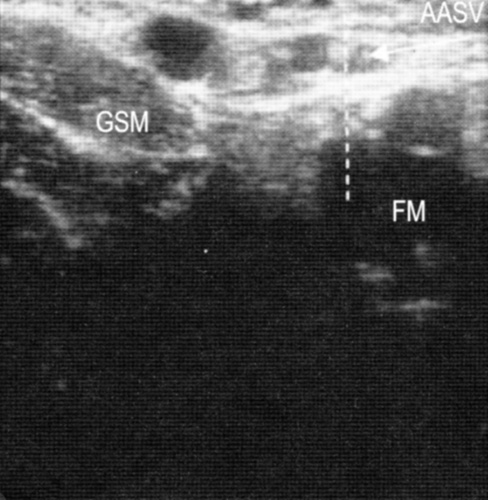

Симптом «глаза» используется для определения вен, располагающихся в расщеплении поверхностной фасции: БПВ, МП, вены Джакомини, латеральной передней подкожной вены.

Диагностика варикоза

Симптом «строя». Большая подкожная вена и ее передний приток (передняя добавочная подкожная вена, ПДПВ) на поперечном срезе, сделанном на уровне верхней трети бедра, часто дают два симптома «глаза». В то же время ПДПВ лежит спереди и латерально по отношению к БПВ. При УЗДГ ее расположение меняется:она находится на одной линии над бедренной артерией и веной.

При УЗДГ в случае аплазии БПВ за симптом «глаза» «отвечает» ПДПВ, о чем можно судить по тому, что он (симптом) располагается над бедренной артерией и веной.